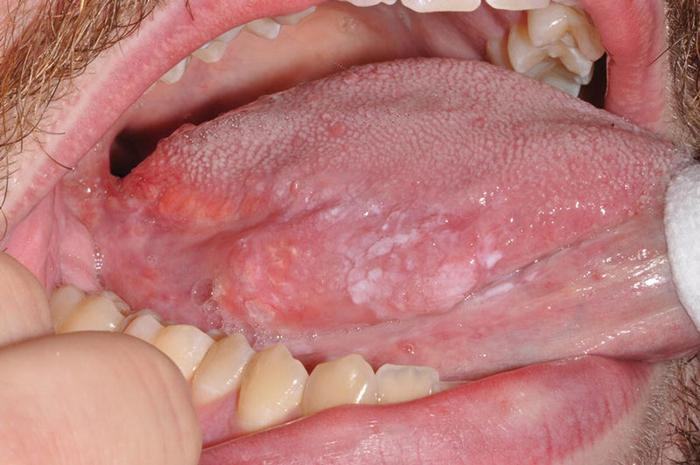

- Ở giai đoạn 2, các vết sần trên lưỡi, má trong,… đã nổi lên nhiều hơn và lan rộng, dễ quan sát hơn. Chúng tạo thành các mảng màu hồng nhẹ hoặc màu trắng, giống như mào gà. Mặc dù chúng nổi nhiều nhưng không gây ngứa ngáy hay đau đớn. Tuy nhiên, khi ăn uống, chúng dễ bị xước, gây chảy mủ hoặc máu.

- Trong giai đoạn 3, bệnh nhân gặp phải những khó khăn nặng nề nhất. Các nốt sần đã phát triển rất lớn và gây ra triệu chứng lở loét, khiến người bệnh cảm thấy đau đớn và khó chịu. Khi ăn uống, thức ăn va chạm với các nốt sần, gây ra chảy dịch và tăng nguy cơ viêm nhiễm. Ngoài ra, bệnh nhân còn phải đối mặt với mùi hôi từ miệng. Trong một số trường hợp, các nốt sần lan ra ngoài miệng, khiến bệnh nhân cảm thấy tự ti và không dám giao tiếp với người khác.